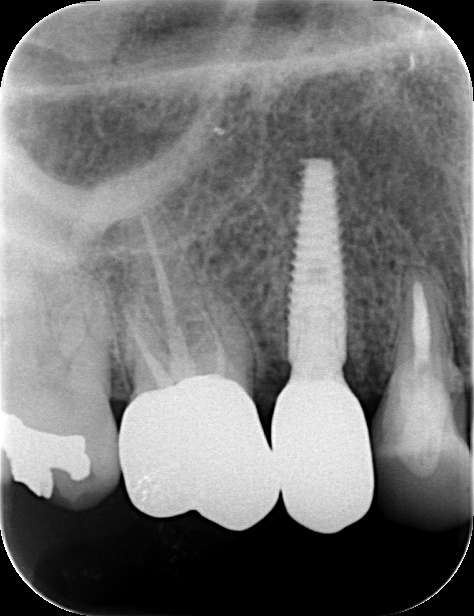

初診時

CT撮影 破折しているのがわかる↑